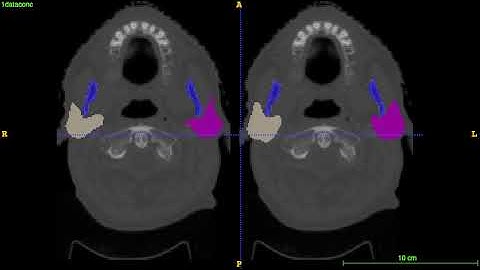

AnatomyNet-for-anatomical-segmentation test demo 3